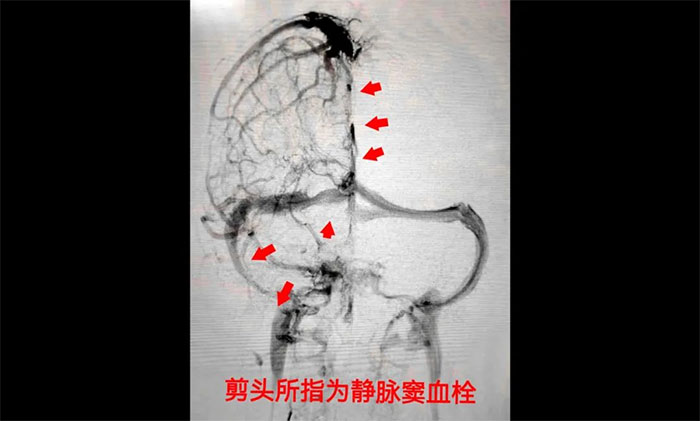

术中,席刚明教授在4A病区副主任王贵平博士协助下,凭借二十多的介入手术经验小心探索,一边“疏通”,一边不断切换正位及侧位造影,避免造成其他损伤。经过3个多小时的奋战,经多次支架取栓、导管抽吸,取出大量暗红色血栓,复查造影见上矢状窦、窦汇、右侧横窦、乙状窦显影改善,患者静脉窦顺利再通。术后,患者症状好转,癫痫未再发作,头痛恶心等症状消失,最终脱离了生命危险,逐步恢复健康。

▲ 颅内静脉窦血栓形成

▲ 术后,静脉窦顺利再通